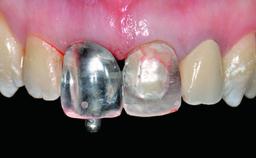

A 28-year-old patient presented at her general dentist’s office and complained about the appearance of her tooth 21. The patient had a history of trauma to this tooth. Endodontic treatment had been performed in the past and a crown placed on the tooth. A procedure to replace the old crown was performed by her dentist; however, a perforation on the middle third of the root occurred, and extraction of tooth 21 was suggested. Upon clinical and radiographic examination of the patient, who had been referred to us, replacement of tooth 21 by a dental implant appeared to be indicated.